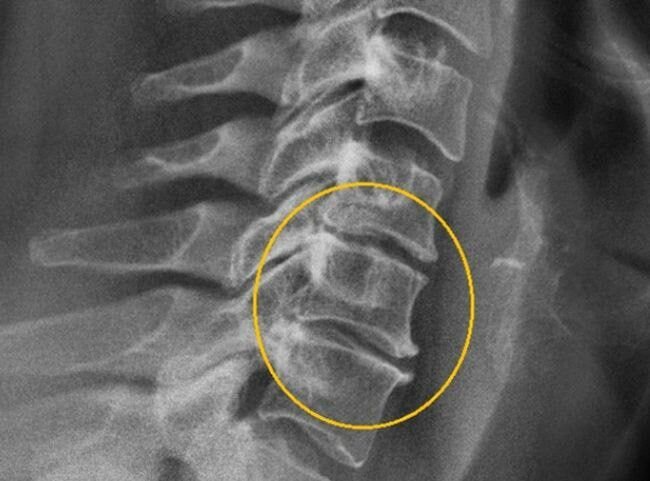

Правда ли, что люди с возрастом «стираются»? Ну, если заменить постановку вопроса, то ответ станет очевидным.  Становятся ли люди с возрастом НИЖЕ? И тут вы можете ответить за нас, ведь все знают, что пожилые люди и правда теряют рост. После 40 лет человек «снижается» каждое десятилетие на 2,5-7 см. Но иногда ситуация может выходить за эти рамки.  Но почему рост человека снижается в старости? Для этого есть несколько причин.  - Потеря мышечной массы и жировых запасов (конкретно это бывает не всегда).  - Остеопороз.  - Уплощение стопы. - Обезвоживание дисков (они находятся между позвонков) — это продемонстрировано на снимке вверху.

- Обезвоживание дисков (они находятся между позвонков) — это продемонстрировано на снимке вверху.